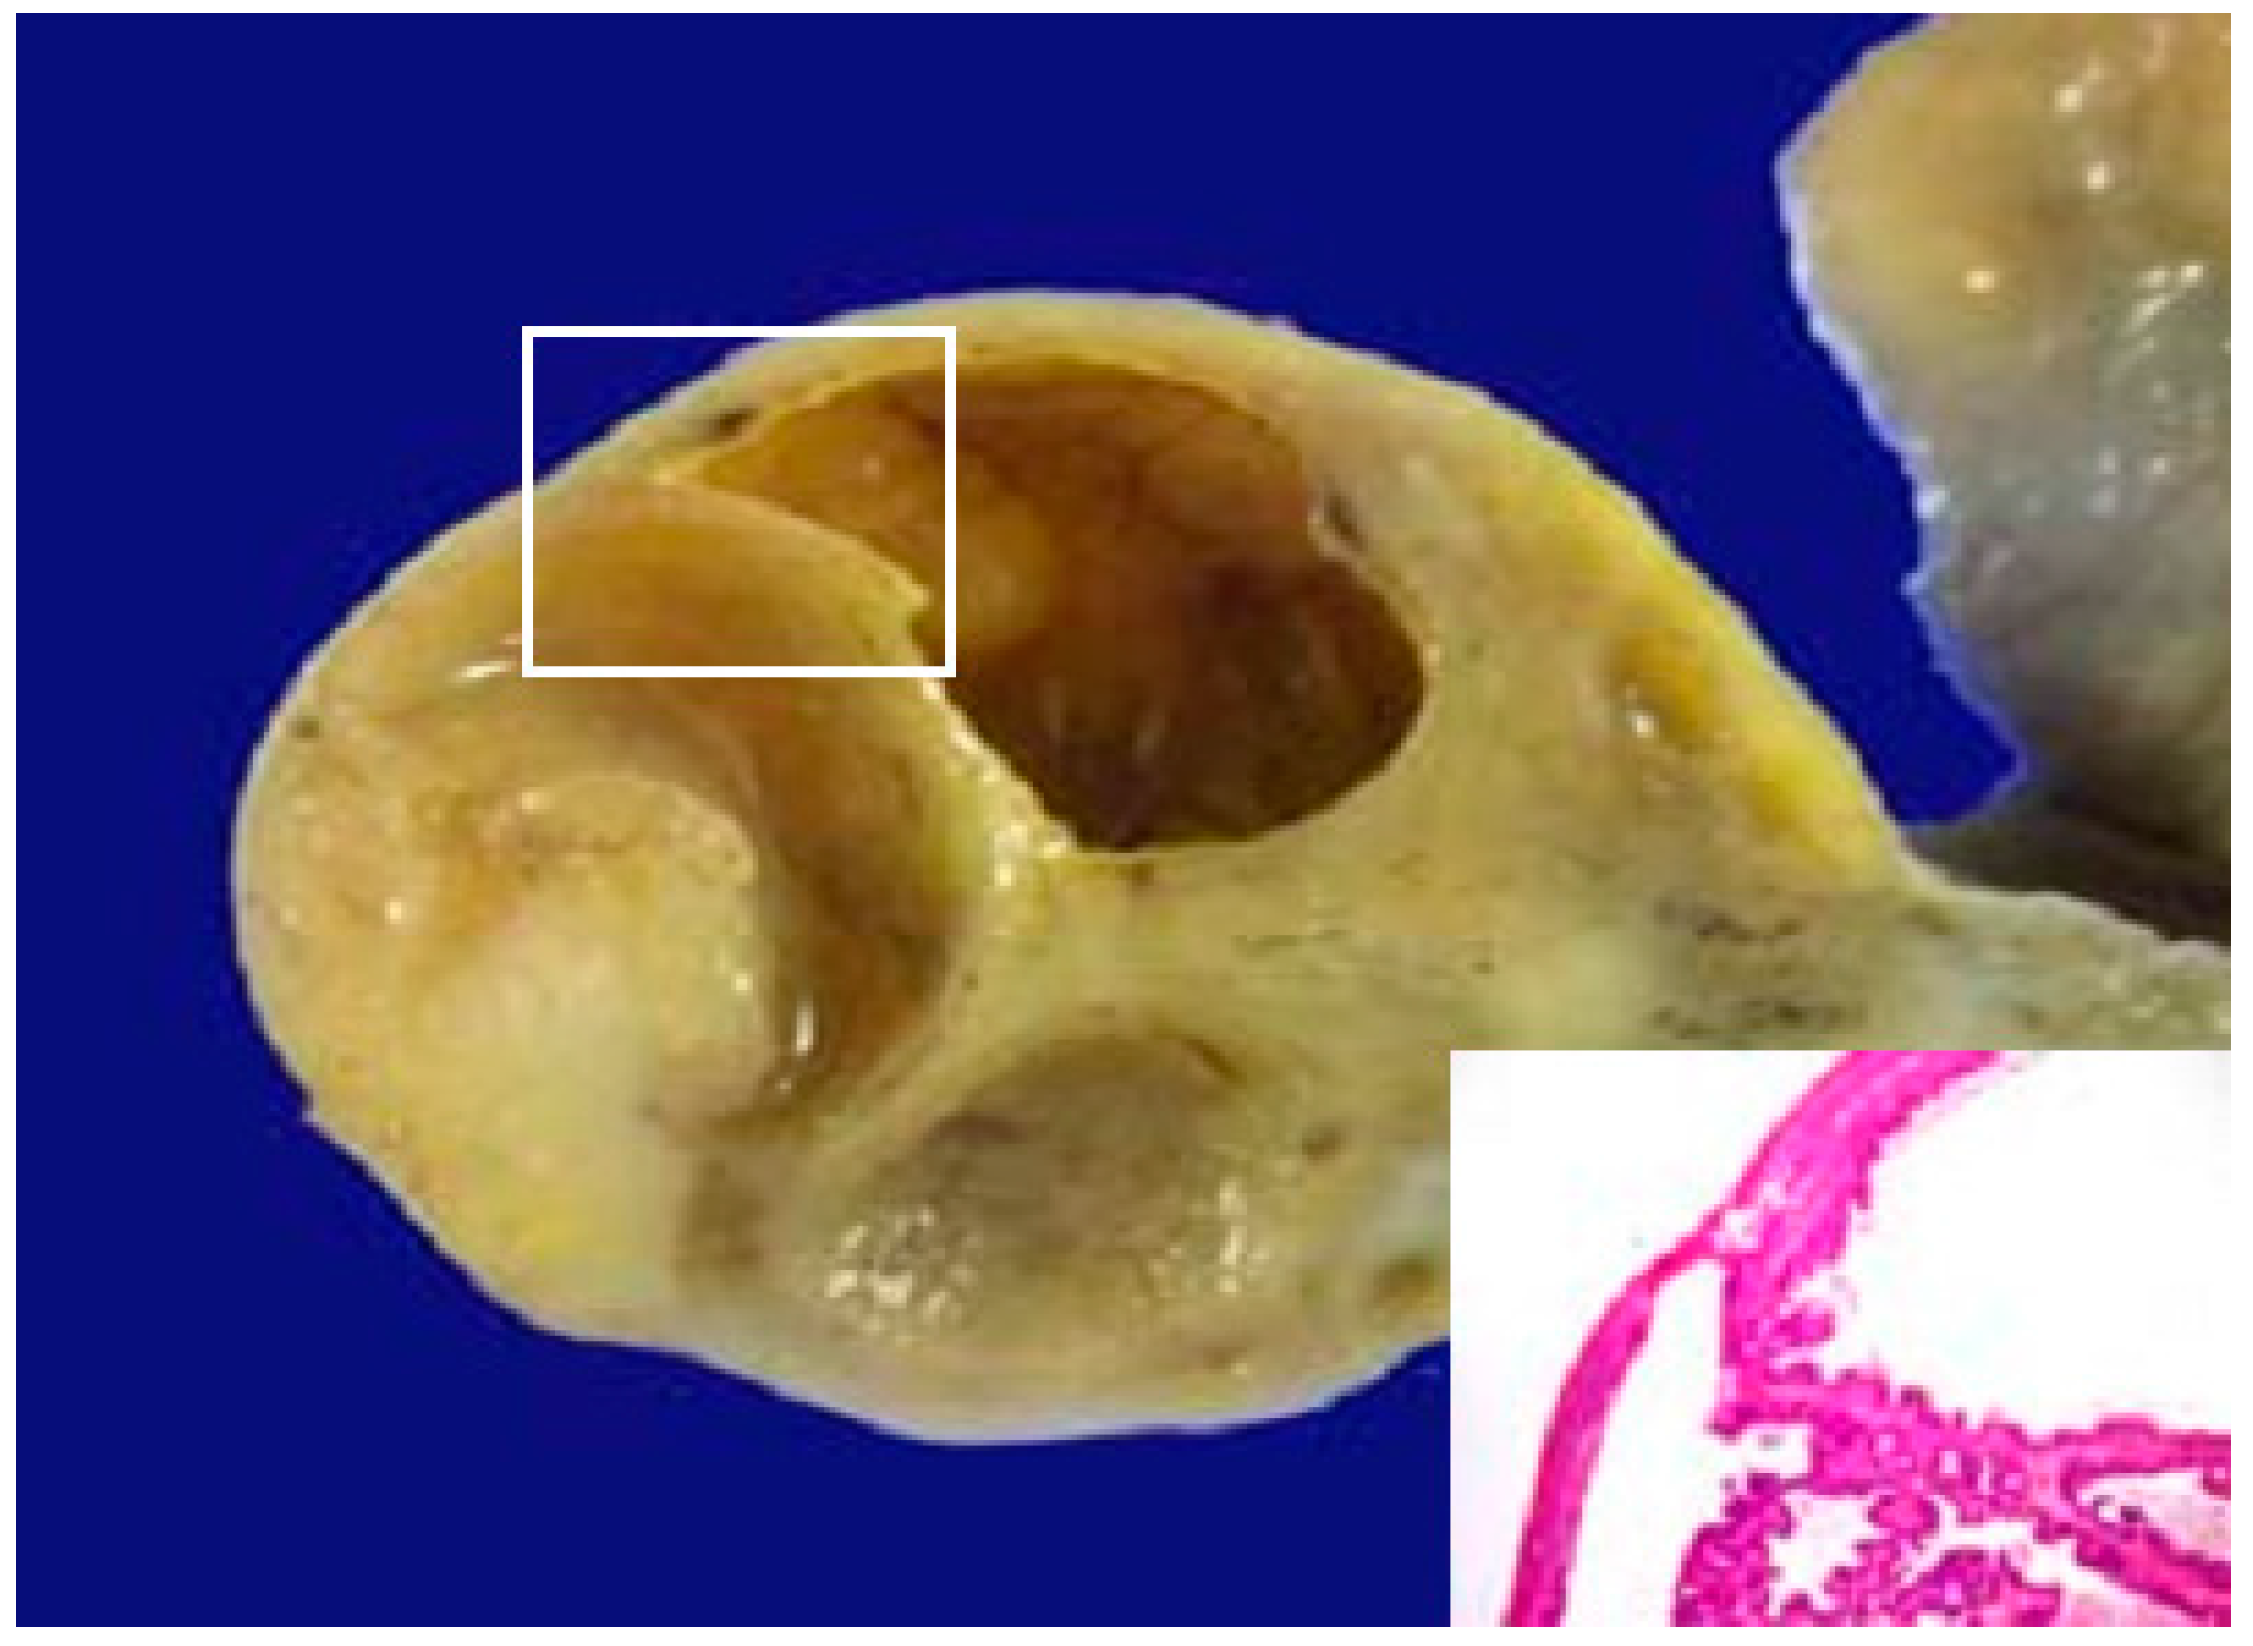

3.2. ALA PDD in Experimental PM

- Yonemura, Y.; Canbay, E.; Ishibashi, H.; Nishino, E.; Endou, Y.; Sako, S.; Ogura, S. 5-aminolevulinic acid fluorescence in detection of peritoneal metastases. Asian Pac. J. Cancer Prev. 2016, 17, 2271–2275. [Google Scholar] [CrossRef] [PubMed]

- Yonemura, Y.; Ishibashi, H.; Sako, S. ALA fluorescence guided surgery. In Comprehensive Treatment for Peritoneal Surface Malignancy with an Intent of Cure; Yonemura, Y., Ed.; Asian School of Peritoneal Surface Oncology: Osaka, Japan, 2014; pp. 110–117. [Google Scholar]

- Murayama, Y.; Ichikawa, D.; Koizumi, N.; Komatsu, S.; Shiozaki, A.; Kuriu, Y.; Ikoma, H.; Kubota, T.; Nakanishi, M.; Harada, Y.; et al. Staging fluorescence laparoscopy for gastric cancer by using 5-aminolevulinic acid. Anticancer Res. 2012, 32, 5421–5427. [Google Scholar] [PubMed]

- Canbay, E.; Ishibashi, H.; Sako, S.; Kitai, T.; Nishino, E.; Hirano, M.; Mizumoto, A.; Endo, Y.; Ogura, S.; Yonemura, Y. Photodynamic detection and management of intraperitoneal spreading of primary peritoneal papillary serous carcinoma in a man: A case report. Surg. Today 2014, 44, 373–377. [Google Scholar] [CrossRef] [PubMed]